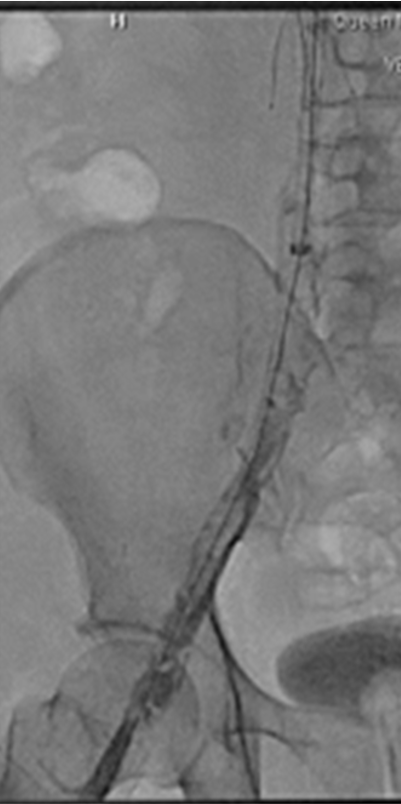

Right internal jugular vein (IJV) and popliteal vein large bore access was obtained with a 14Fr sheath and a 16Fr ClotTriever sheath respectively. Initial venogram showed extensive thrombosis from the below knee popliteal vein to the IVC filter with flow stasis of the intravenous contrast.

Through and through wire was achieved from popliteal to IJV and the 14fr IJV sheath was advanced past the IVCF struts to act as a protection for the basket and coring element of the ClotTriever for thrombectomy of the IVC and iliofemoral veins as several passes were made. There was satisfactory clearance of clots from the left iliofemoral veins. Aspiration of the IVCF was then performed with a FlowTriever 16 catheter but there was incomplete thrombectomy with some of the remnant clots being pushed above the IVC filter. The IJV sheath was upsized to 16F over and the sheath was used to protect the ClotTriever as it passed though the filter. The through and through Rosen wire (Cook Medical, Bloomington, Indiana) was subsequently pulled back from the IJV and cannulated into the right subclavian vein. The ClotTriever was then deployed next to the 16Fr sheath above the filter as an embolic protection device. The thrombosed IVC filter was then retrieved with a Clover snare (Cook Medical, Bloomington, Indiana). From the IJV sheath, FlowTriever disks were deployed and further thrombectomy of the remnant IVC thrombus was performed which yielded even more thrombus.

Completion venogram showed brisk return of flow and patency.